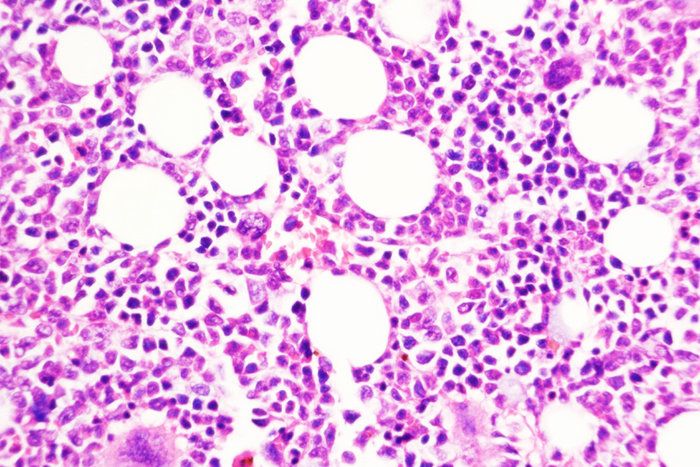

圖片:圣路易斯華盛頓大學醫學院的一項研究提出了一種預防慢性、生長緩慢的血癌發展為侵襲性白血病的策略。圖中顯示的是用一種化合物阻斷DUSP6的小鼠骨髓,DUSP6是由慢性疾病轉變為侵襲性疾病的關鍵分子。

來源:Tim Kong, Angelo Laranjeira

使用遺傳技術刪除DUSP6基因可以防止這種癌癥模型小鼠向侵襲性疾病的轉變。研究人員還測試了一種抑制DUSP6的藥物化合物,并發現這種化合物(僅用于動物研究)在兩種不同的癌癥小鼠模型和從患者身上取樣的人類腫瘤小鼠中阻止了慢性疾病向侵襲性疾病的進展。在這些模型中,通過基因和藥物降低DUSP6水平也能減少炎癥。